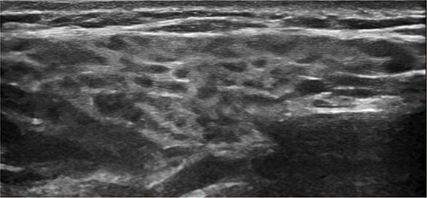

Fig. 2: Échographie de la glande parotide, grade 2 selon l’OMERACT: manques d’uniformité de la texture de la glande parotide avec de multiples zones hypo- à anéchogènes qui sont encore entourées de tissu normal

Les techniques d’imagerie telles que l’échographie des glandes parotide et submandibulaire ont pris de l’importance au cours des dernières années, car elles sont sensibles, non invasives et rapides à réaliser. Sur l’image B, une sonde linéaire de 10 à 18 MHz permet de constater des manques d’uniformité plus ou moins marqués du parenchyme des glandes salivaires, avec des zones arrondies focales hypo- ou anéchogènes (Fig.2). La classification de ces modifications en différents grades (0–3) par l’OMERACT («Outcome Measures in Rheumatology Clinical Trials») a été largement acceptée au niveau international.12 L’échographie compare les glandes salivaires au parenchyme de la thyroïde, qui doivent normalement être homogènes et isoéchogènes entre elles. L’hypervascularisation peut également être quantifiée par doppler couleur et classée en différents grades (0–3) selon l’OMERACT.13 Il convient de s’abstenir de manger et de mâcher au moins une heure avant, car le processus de mastication stimule physiologiquement la circulation sanguine.

Un article de synthèse systématique avec méta-analyse a montré que l’échographie des glandes salivaires présente une sensibilité groupée de 80% (IC à 95%: 77–83%) ainsi qu’une spécificité de 90% (IC à 95%: 87–92%) pour le diagnostic.14 Une autre étude a en outre constaté une forte concordance des résultats de l’échographie avec les résultats de la biopsie de la glande parotide (83%) ou de la lèvre inférieure (79%). Dans leur étude, un résultat d’échographie pathologique combiné avec la détection d’auto-anticorps anti-Ro/SSA ou une échographie normale combiné avec l’absence de ces anticorps était particulièrement significative: les deux constellations présentaient une valeur prédictive élevée pour le diagnostic de la maladie de Sjögren ou son exclusion.15